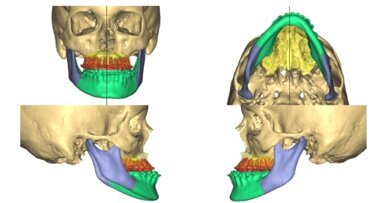

Technologia 3D oraz CAD/CAM są coraz częściej wykorzystywane do planowania operacyjnego leczenia szkieletowych wad zgryzu. Technologia 3D i CAD/CAM są ...